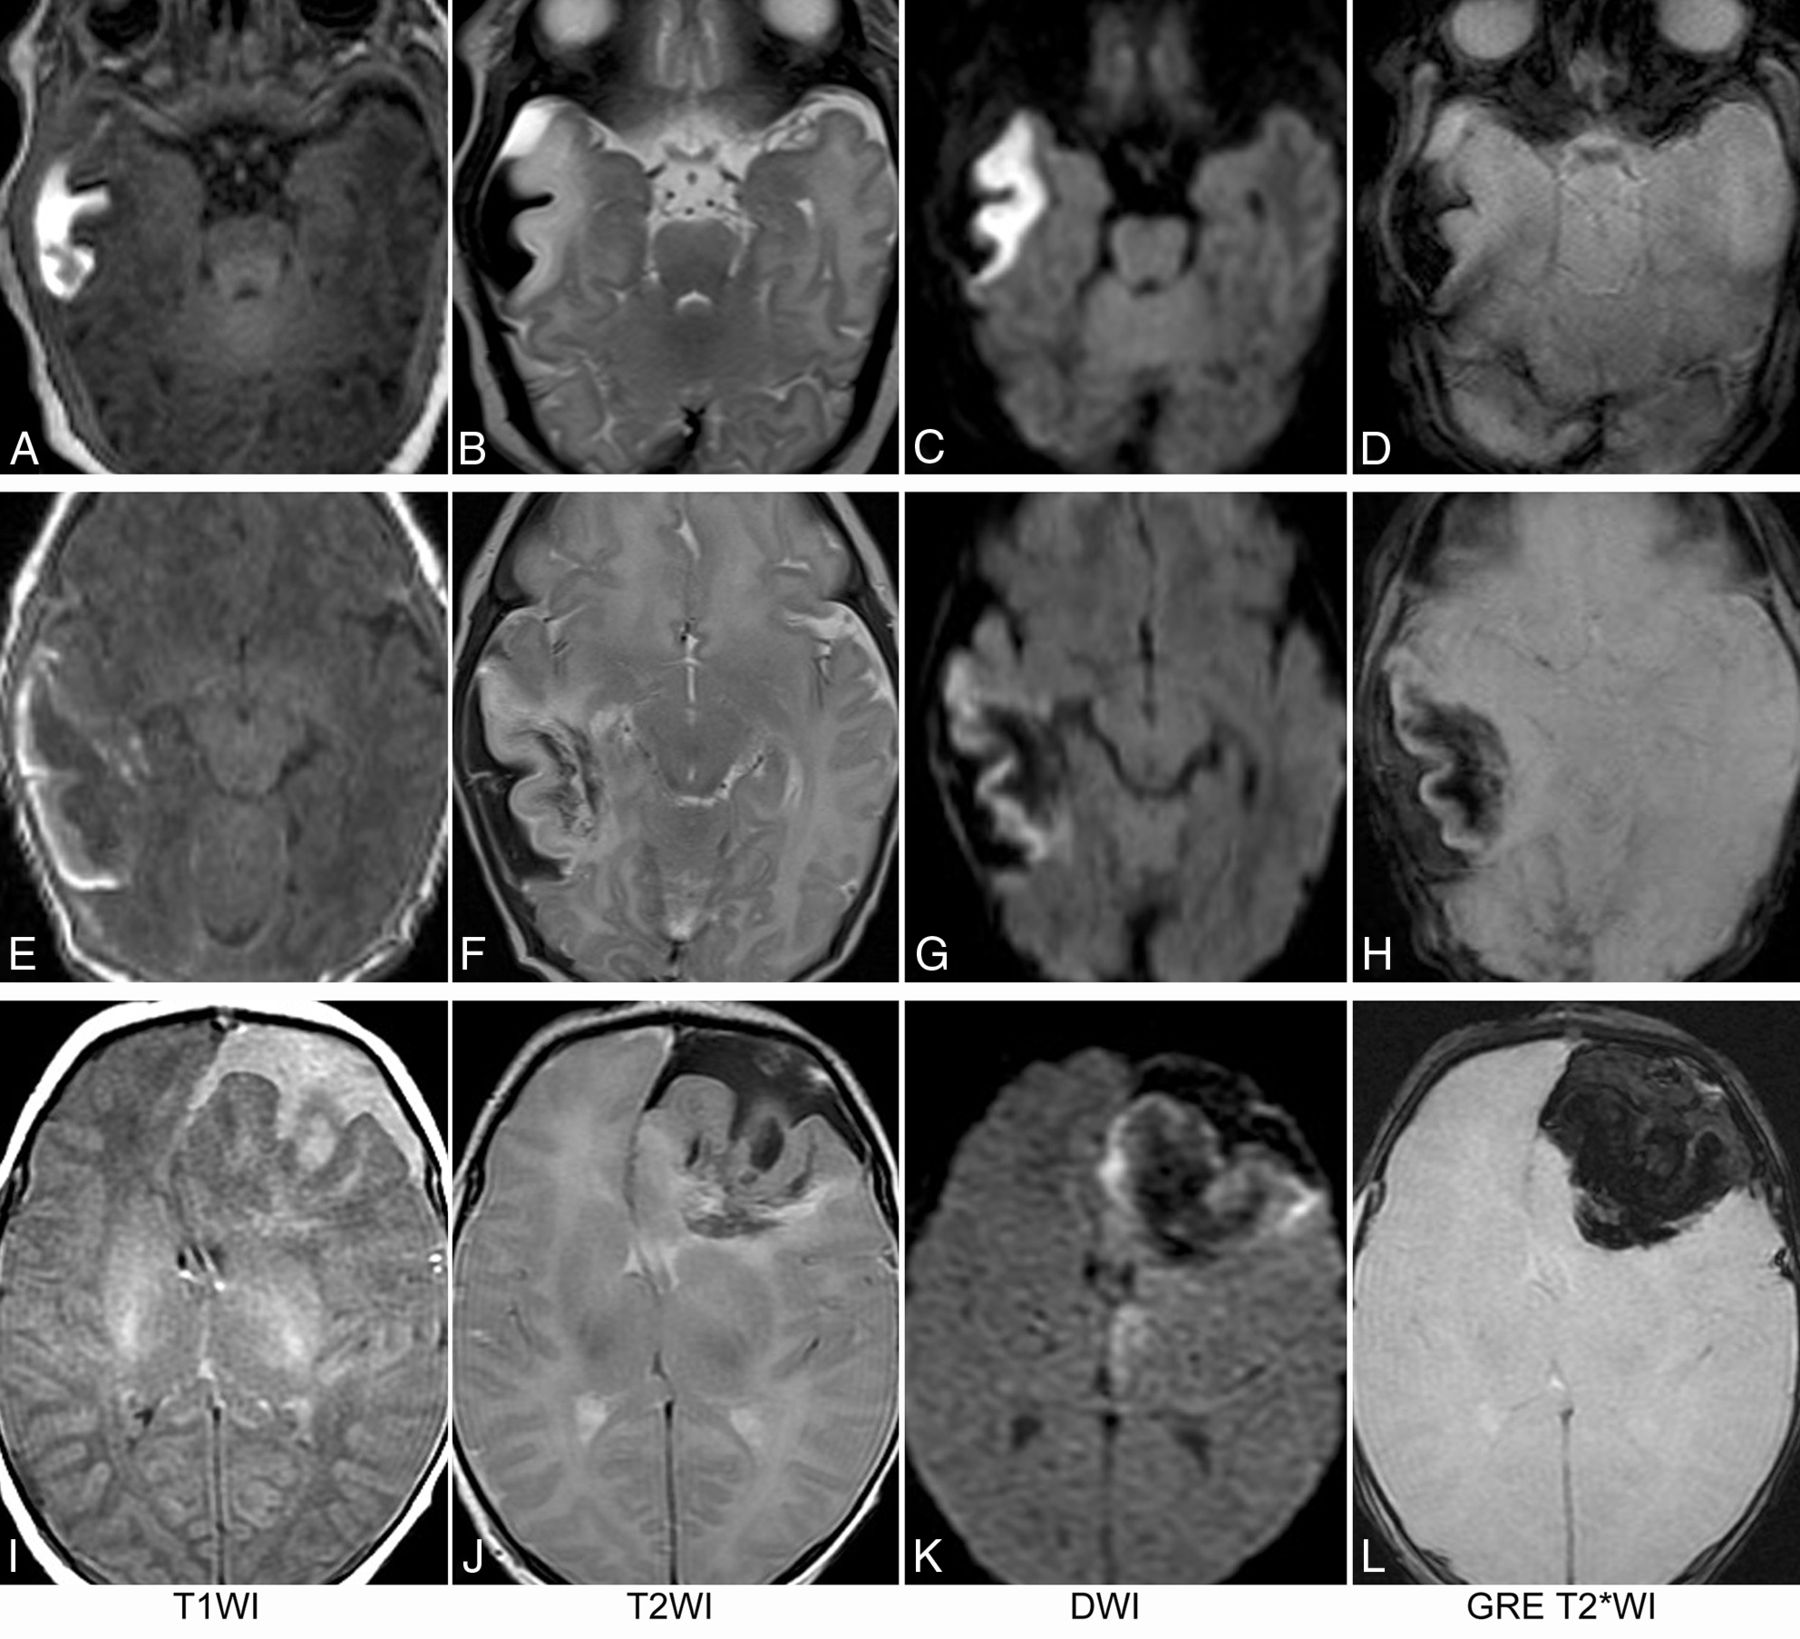

On the initial MR imaging, irrespective of the location and size of the lesion, 2 key components were consistently seen on all MR images. The first was a focal subpial collection of fluid extending into the adjacent cerebral sulci associated with widening of the cerebral sulci and flattening of the underlying parenchyma. The subpial collection consistently demonstrated mild-to-moderately hyperintense T1 signal, markedly hypointense T2 signal, and increased diffusivity on DWI and ADC maps, consistent with acute or subacute bleed (Fig 2).

MR images of 3 term neonates. The subpial hemorrhage consistently shows hyperintense T1 signal, hypointense T2 signal, no restricted diffusion, and hypointense signal on GRE T2*WI. In the first patient (A–D), the underlying cerebral cortex and white matter have no hemorrhage. In the second patient (E–H), a mild fan-shaped hemorrhage is seen in the underlying white matter, resulting in a hypointense signal on T2WI, DWI, and T2*WI, while the cerebral cortex remains hyperintense on T2WI, DWI, and T2*WI. In the third patient (I–L), more severe hemorrhage is seen in the underlying white matter, leading to an obscured cerebral cortex on T2*WI and a partially obscured cortex on DWI.

The second component of the lesion was signal change in adjacent brain parenchyma. This included the cortex as well as subcortical and deeper white matter immediately underneath the subpial hemorrhage. On 4 of 15 MR imaging scans, no intra-axial hemorrhage was present in the parenchyma. In these cases, both the cortex and white matter lesions consistently demonstrated uniformly hypointense T1 signal, hyperintense T2 signal, restricted diffusion, and isointense signal on GRE T2*WI or SWI (Fig 2A–D). On 6 of 15 MR imaging scans, a small amount of hemorrhage was present in the subcortical and deep white matter components of the lesion. In these cases, the involved cortex consistently demonstrated hypointense T1 signal, hyperintense T2 signal, restricted diffusion, and isointense signal on GRE T2*WI, while the underlying white matter showed heterogeneous signal on T1WI and T2WI and was predominantly hypointense on DWI and GRE T2*WI (Fig 2E–H). On the remaining 5 MR images, a larger amount of hemorrhage was present in the subcortical and deep white matter. In these cases, the involved cortex consistently demonstrated hypointense T1 signal, hyperintense T2 signal, and restricted diffusion and large blooming artifacts on GRE T2*WI. The underlying white matter demonstrated heterogeneous signal on T1WI and T2WI and was predominantly hypointense on DWI and GRE T2*WI (Fig 2A–D). The signal characteristics of each group are summarized in Table 3.

On T2WI and DWI, the consistent presence of a dark, hypointense, subpial bleed and an underlying bright, hyperintense cerebral cortex created a distinct MR imaging pattern, resembling the yin-yang symbol in Chinese philosophy (Fig 3).

Yin-yang sign. T2WI and DWI of 3 term neonates with subpial hemorrhage are shown. In the brain parenchyma underlying the subpial bleed, no hemorrhage is seen in the first patient (A and B); mild hemorrhage, in the second patient (C and D); and severe hemorrhage, in the third patient (E and F). Irrespective of the presence or degree of intraparenchymal hemorrhage, the combination of a dark subpial fluid collection and a bright underlying cerebral cortex forms a consistent, distinct image pattern (circled areas in A–F), resembling the yin-yang symbol in Chinese philosophy.